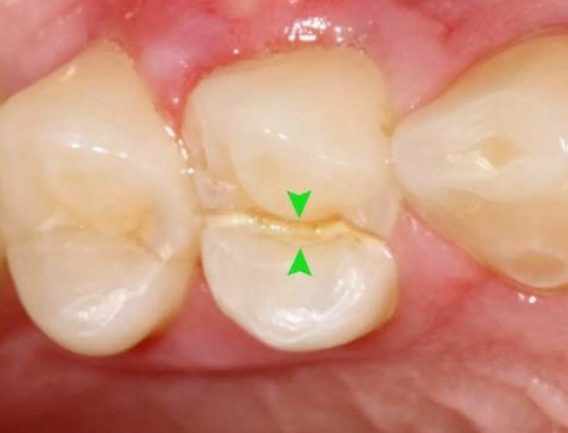

于是抱著僥幸心理,讓牙齒在沒有“防護(hù)衣”的情況下:咬著小堅(jiān)果,嗑著小瓜子……有一天,“咔”!牙齒劈裂了!

02、根管調(diào)節(jié)的適應(yīng)癥牙髓炎:牙髓因細(xì)菌感染而發(fā)炎。在密封的牙髓腔中,牙髓通常不會(huì)被細(xì)菌感染。當(dāng)牙齒因齲齒而開孔時(shí),該孔太深,外部細(xì)菌會(huì)侵入牙髓腔,從而感染骨髓。根尖周炎:牙髓感染細(xì)菌后,細(xì)菌將通過根尖孔侵入牙槽骨,導(dǎo)致根尖周圍組織發(fā)炎。只要去除感染的牙髓,根尖的炎癥就會(huì)消退。牙髓裸露:當(dāng)牙齒折斷并且牙齒的神經(jīng)暴露時(shí),通常需要進(jìn)行根管調(diào)節(jié)。03、根管調(diào)節(jié)的步驟1、術(shù)前拍攝X線片:在根管調(diào)節(jié)過程中,在根管調(diào)節(jié)術(shù)前拍X線片,可以幫助診斷,了解髓室的位置和根管數(shù)目及形態(tài),測(cè)量根管工作長(zhǎng)度。